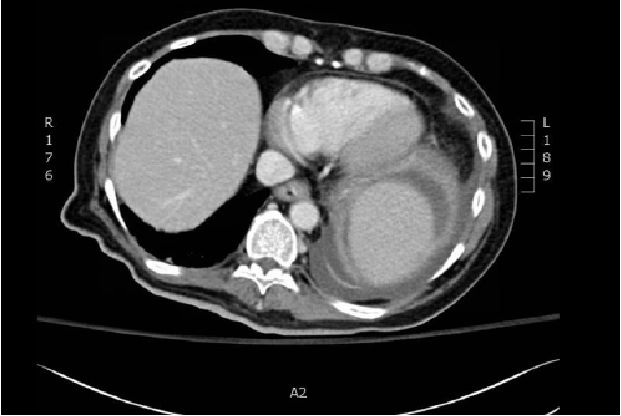

一例74岁患有原发性十二指肠间质瘤(GIST)的女性患者因心源性休克收入我院急诊科,死于心外肿瘤破裂导致的心脏骤停。冠状动脉CT血管造影(图A)显示肿瘤有来自右冠状动脉和左前降支的营养血管。心血管磁共振(图B)显示肿瘤(箭头)具有不均匀强化,起自心肌。患者选择接受保守治疗。尸检于心室浆膜下检测到一个7×8×7厘米的弹性软肿瘤。病理示呈纤维样增生的轻度非典型梭形细胞(图C),CD117(c-kit)阳性(图D)。因此,该心外肿瘤被诊断为GIST转移。虽然三分之二的GIST转移患者为肝转移,心脏转移较罕见。